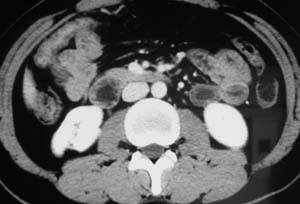

以下是引用子期在2010-3-19 20:47:00的发言:[br]血管畸形的ct增强应该有明显强化,本例并不相符合。本例双肾局部的略低密度影,累及肾盂,局部皮质明显变薄、内陷,增强扫描有轻度的强化,应考虑为炎性病变,患者为年轻男性,累及双肾的感染以结核较常见,可以没有明显的临床症状,尿中有时候也并不能查出什么;肾脓肿常有明显感染中毒症状,本例不符,另外一般的肾盂肾炎或肾小球肾炎通过小便就可确诊,其它还不能排除的是黄色肉芽肿性肾盂肾炎,然而单凭ct一般也很难鉴别。